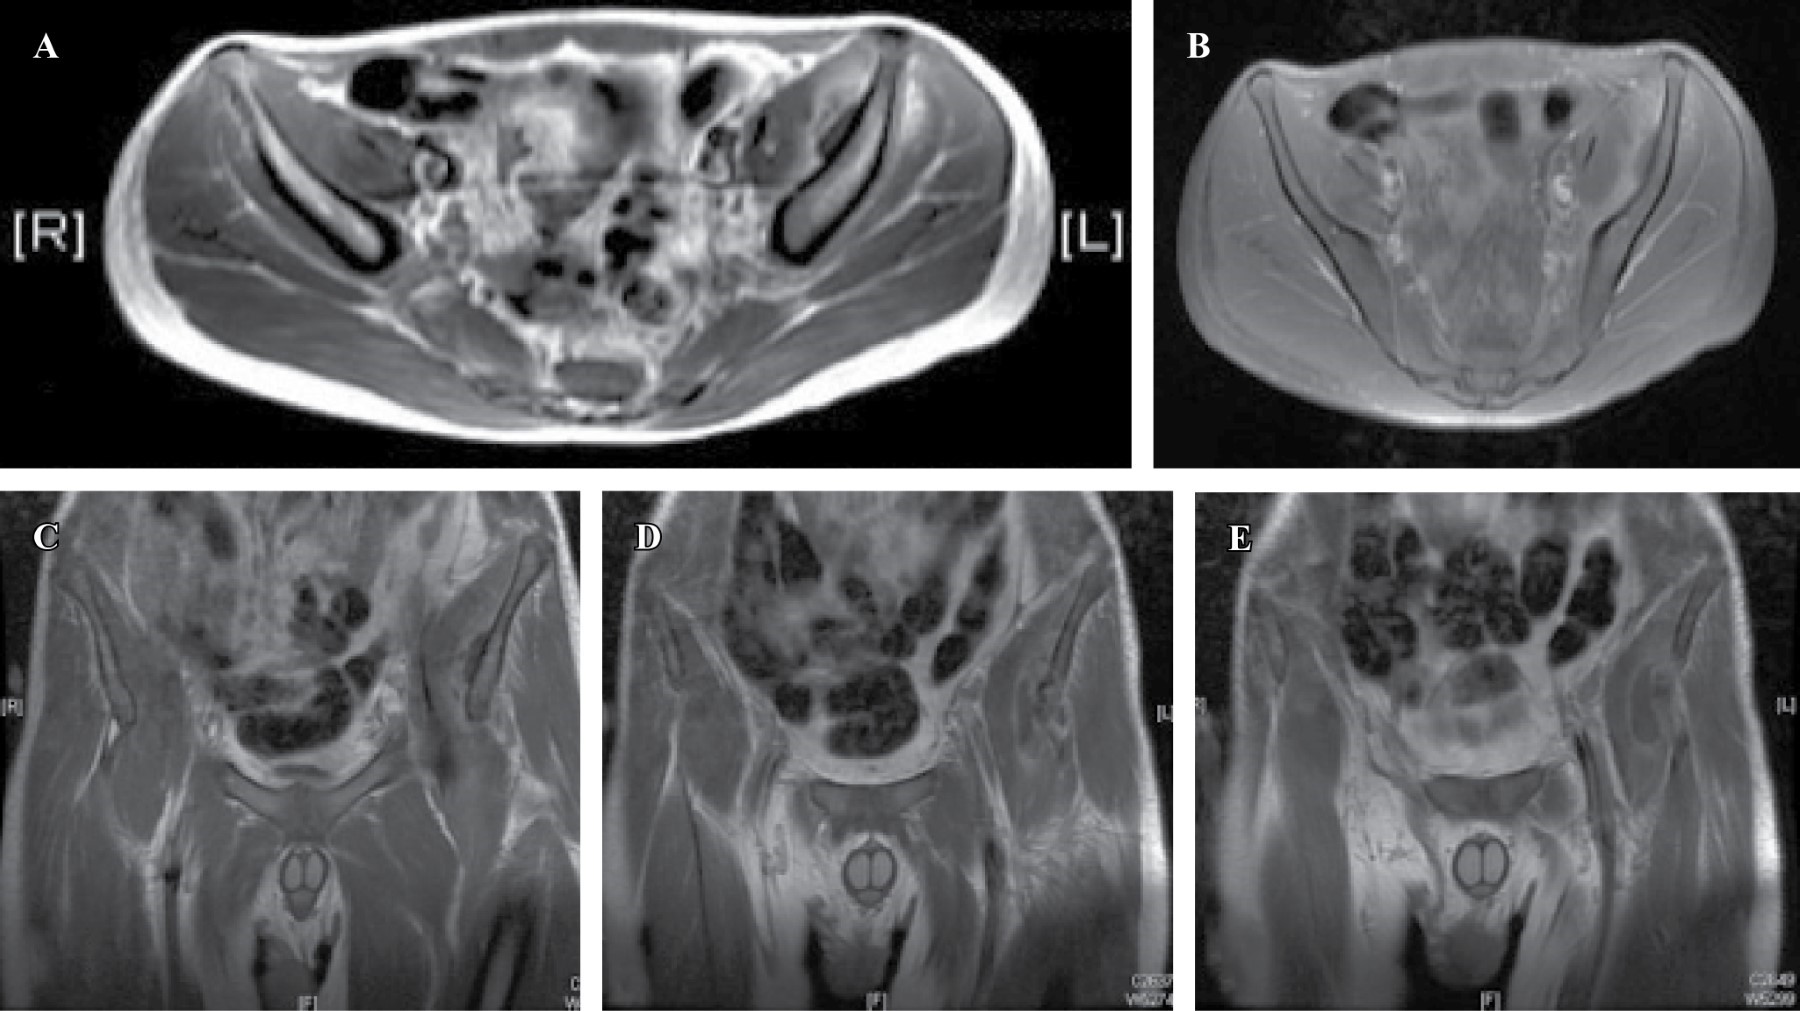

Tropical pyomyositis of the iliacus, obturator internus, piriformis and psoas major muscles in an immunocompetent patient with claudication

Sánchez-Rodríguez H, Morales-Ávalos R, Rivera-Zarazúa S, Ramírez-Elizondo M, Hernández-Rodríguez P, Vílchez-Cavazos F, Peña-Martínez V

Introduction: Pyomyositis is a term that denotes pyogenic infection usually primary skeletal muscle, associated with hematogenous dispersion due to transient bacteremia, or penetrating trauma, usually forming abscesses. Classically described frequently in tropical areas and predominantly affecting the lower limb musculature, however, in recent decades it has increasingly been associated with areas of temperate climates and relatively more frequently in immunosuppressed patients, being the patients under 30 years the most affected. Clinical case: Male of 15 years without relevant medical history. The patient had no history of trauma, falls, surgical interventions, infections or any other systemic condition. He came because of a clinical picture of 7 days of evolution characterized by pain referred to the groin and left iliac crest area associated with claudication and hyperthermia not quantified, which yielded partially to NSAIDs and paracetamol, but without achieving improvement so it is taken emergency by relatives. Conclusions: It is necessary to bear in mind this pathology when performing the differential diagnostic approach of a patient presenting with pain and functional limitation of some joint associated with data suggestive of an infectious or inflammatory process.

Figure 1